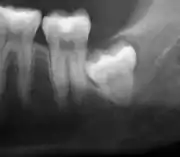

Panoramic radiograph of impacted lower wisdom teeth (green arrows) in a 26-year-old with dental caries (red arrows) on the adjacent teeth

The diagnosis of impaction can be made clinically if enough of the wisdom tooth is visible to determine its angulation, depth, and if the patient is old enough that further eruption or uprighting is unlikely. Wisdom teeth continue to move to the age of 25 years old due to eruption, and then continue some later movement owing to periodontal disease.[18]

If the tooth cannot be assessed with clinical exam alone, the diagnosis is made using either a panoramic radiograph or cone-beam CT. Where unerupted wisdom teeth still have eruption potential several predictors are used to determine the chance of the teeth becoming impacted. The ratio of space between the tooth crown length and the amount of space available, the angle of the teeth compared to the other teeth are the two most commonly used predictors, with the space ratio being the most accurate. Despite the capacity for movement into early adulthood, the likelihood that the tooth will become impacted can be predicted when the ratio of space available to the length of the crown of the tooth is under 1.[5]:141